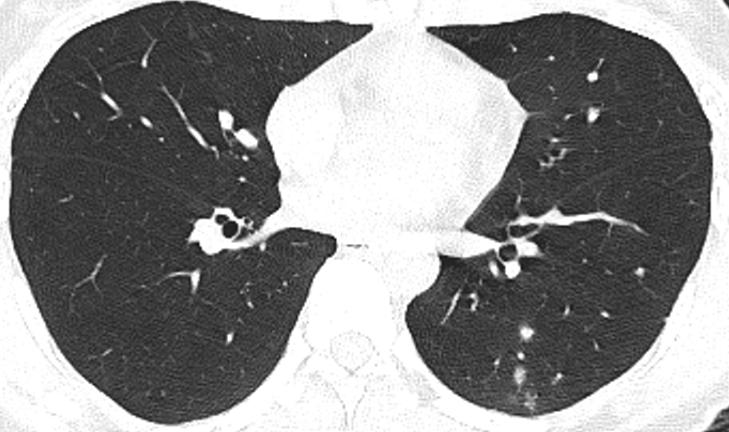

胸部CT示:双肺多发磨玻璃结节,左下叶背段散在实性结节,散在小空洞,部分支气管的管壁增厚,如下(图1~17)。